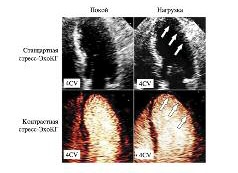

Исходно при стандартном исследовании отмечались нарушения сократимости в 68 сегментах (в 41 – гипокинезия, 22 – акинезия, 5 – дискинезия), при исследовании с контрастным препаратом – в 93 сегментах (в 56 – гипокинезия, 29 – акинезия, 8 – дискинезия). На пике нагрузки при стандартной стресс-ЭхоКГ нарушения сократимости выявлены в 126 сегментах (в 83 – гипокинезия, 35 – акинезия, 8 – дискинезия), а после введения контрастного препарата – в 190 сегментах (в 120 – гипокинезия, 58 – акинезия, 12 – дискинезия). Таким образом, введение контрастного препарата позволяет с большой уверенностью не только обнаруживать нарушение локальной сократимости миокарда, но и оценивать его выраженность как в покое, так и во время нагрузки. Пример сравнения стандартной стресс-ЭхоКГ и МКСЭ представлен на рис. 3.

Рис. 3. Четырехкамерная апикальная позиция: сравнение стандартной стресс-ЭхоКГ и МКСЭ у пациента с неудовлетворительной визуализацией эндокарда ЛЖ. При введение контрастного препарата выявлялась зона гипокинезии по боковой стенке ЛЖ (указана стрелками), которая четко не определялась при стандартной стресс-ЭхоКГ.

Анализ перфузии миокарда был возможен в 384 сегментах ЛЖ. Из них снижение перфузии в покое наблюдалось в 63 сегментах, а отсутствие – в 15. На пике нагрузки количество сегментов ЛЖ с нарушенной перфузией увеличилось до 109 и 34 сегментов соответственно. При этом зона дефекта перфузии миокарда превышала зону нарушения локальной сократимости в 14 (3,6%) сегментах в покое и в 24 (6,2%) сегментах на пике нагрузки, а также выявлялась в областях с нормальной сократимостью в 9 (2,3%) сегментах в покое и в 13 (3,3%) сегментах на пике нагрузки. Пример приведен на рис. 4.